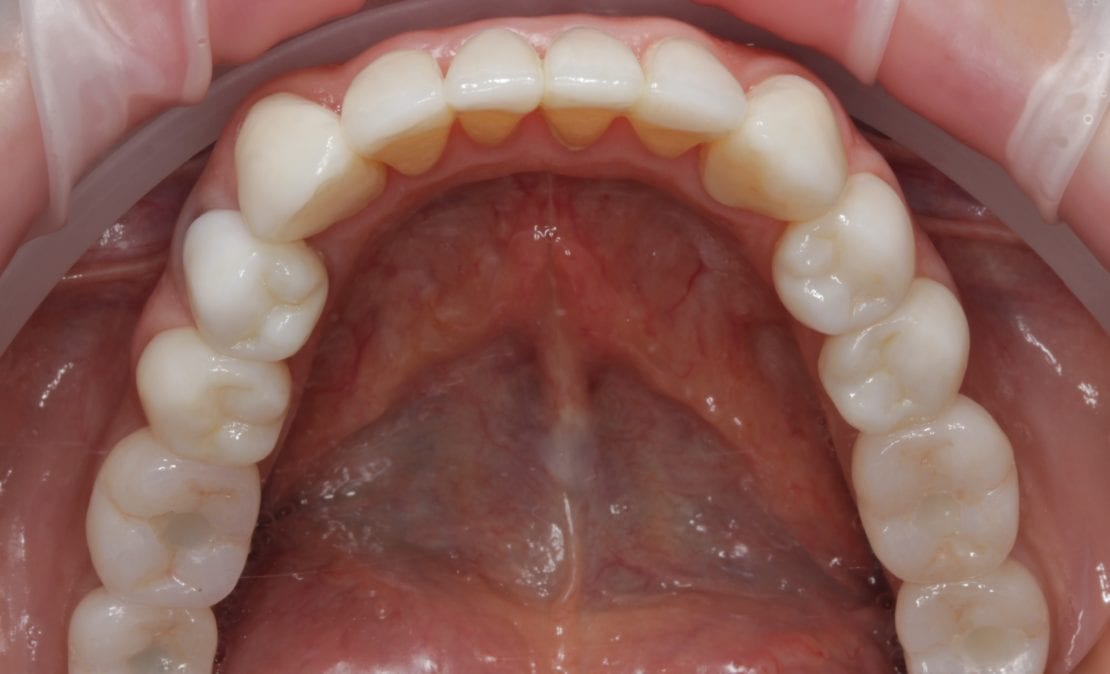

Пациентка 50 лет обратилась для замены старого съемного протеза верхней челюсти на новый несъемный (с просьбой об имплантации). После тщательной диагностики хирургом Борискиным А.А. и ортопедом Березиным А.И. была проведена одномоментная имплантация с нагрузкой временным несъемным протезом в первые дни после операции, что позволило пациентке почти не отвлекаться от работы, и получить несъемную конструкцию на верхней челюсти впервые за долгие годы. После достижения интеграции (не менее 6 месяцев) временные конструкции были заменены ортопедом на постоянные — цифровые из диоксида циркония с титановой балкой. Достигнута идеальная интеграция с мягкими тканями, эстетическая реабилитация и переход в желаемый цвет без затрагивания нижних передних зубов (пожелание пациентки).